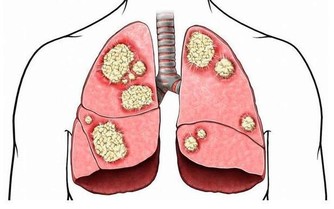

據美國紐約一家專門從事癌癥研究的權威機構透露,中國和日本婦女乳腺癌的發病率比西方低得多,這是為什麼呢?

科學家在比較了世界各國的三餐食譜後得出結論:是由於中國和日本婦女多吃大白菜的緣故。

調查資料表明,每10萬名婦女中,每年乳腺癌的發病率為:中國9人,日本21人,北歐84人,美國91人。

實驗證明,大白菜所含有的許多物質、具有防癌抗癌的作用,因此在美國國立癌癥研究所、發表的防癌食品排行榜中、將白菜排在僅次於大蒜的後面,名列第二。。

其次,大白菜含有一種叫做吲哚-3-甲醇的化合物,其含量約佔大白菜重量的0.01%,它能促進人體產生一種重要的酶,這種酶能夠有效抑製癌細胞的生長和分裂。

能夠防止致癌物亞硝銨合成的微量元素鉬、大量存在於大白菜中,能阻斷亞硝胺等致癌物質在人體內的生成,所以能防止癌癥的發生。

據測算,每天吃1磅大白菜,或白菜榨汁,每天飯後服200-300克,就能吸收到500毫克這種化合物,達到預防癌癥的目的。